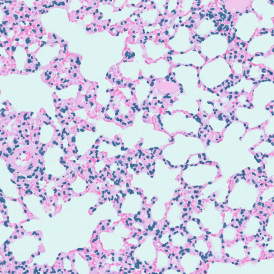

The Pulmo App segments nuclei and the metastructure components of the lung, including tissue, bronchioles, blood vessels, and alveoles. Each segmented metastructure is measured for up to 20 morphometric parameters.

App Category 3